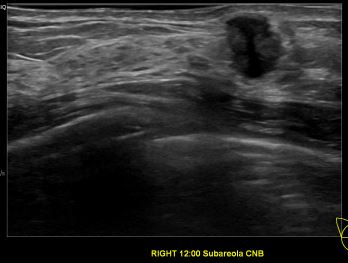

상기환자는 외부검진이상소견 조직검사위해 내원하신 60대 초반

여성분으로 의심스러운 우측유방혹 조직검사 시행해 침윤성암으로 진단되었습니다